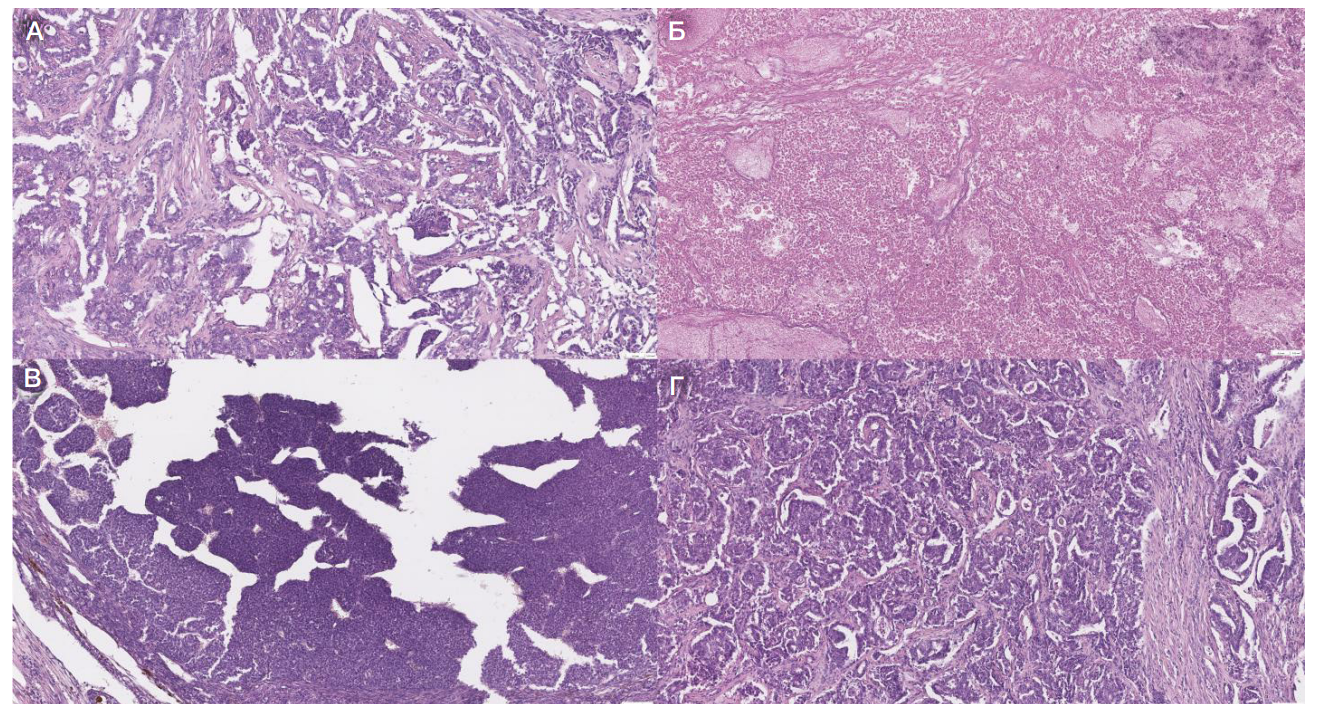

Рис. 2. Микрофотография среза опухолевых образцов, полученных от лабораторных животных № 7 (А), № 8 (Б), № 9 (В) и № 6 (Г), при увеличении 10×. Срезы окрашены гематоксилином и эозином